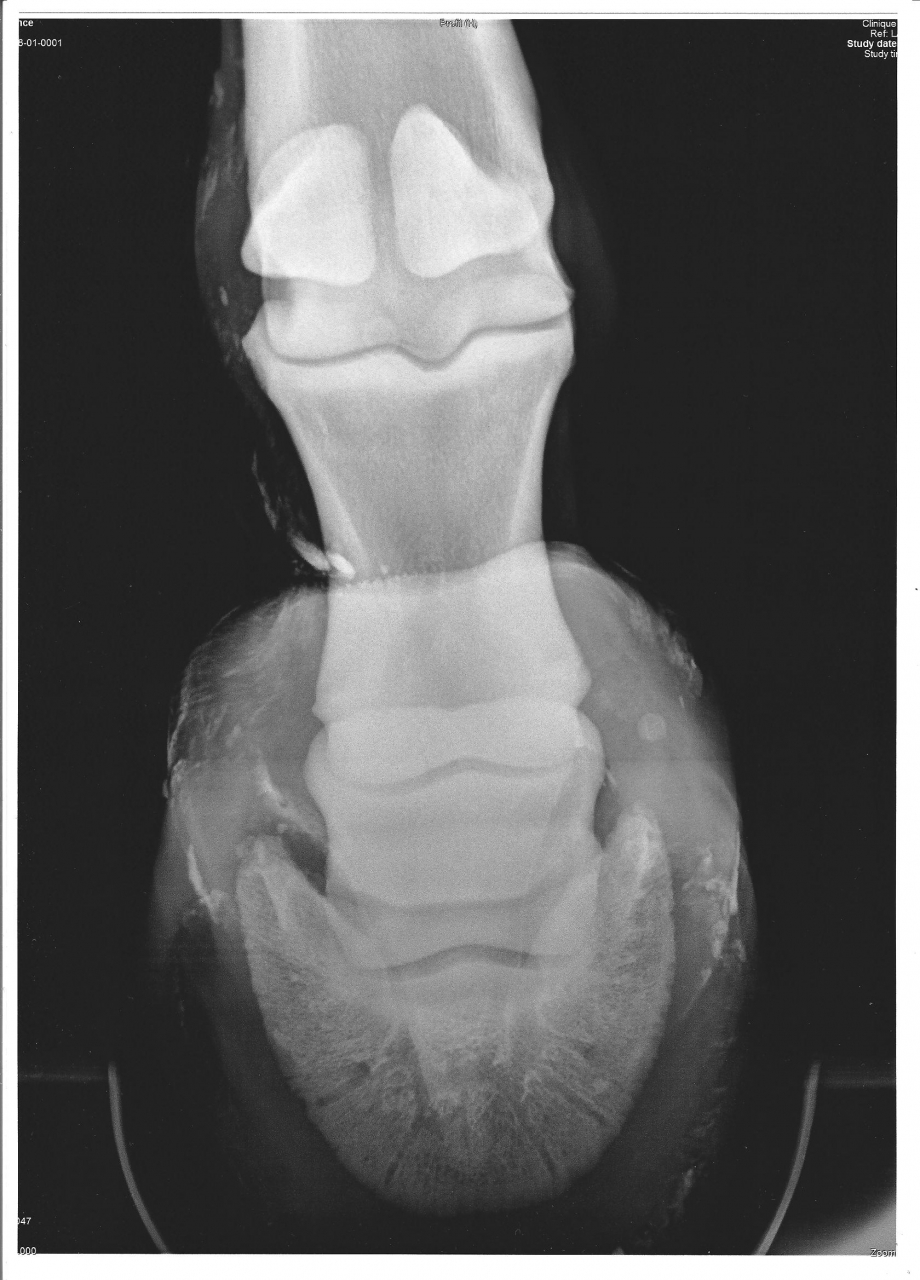

| Dire merci | Sur un fjord de 10 ans, pas gros : Il y a un moment ( découverte il y a 2 ans, mais sans doute plus ancienne ) que mon loulou à carrément une fracture du processus palmaire qui ne se ressoudera sans doute pas, découverte par hazard car on avait fait des radios pour savoir d'où venait sa boiterie et ce n'était même pas de là, il avait le garrot de bloqué... mon véto m'a donner le feu vert pour le monter et travailler normalement mais j'ai peur que le bout non ressoudé bouge à un moment ou à un autre et fasse de gros dégas... Vue que depuis il s'est encore blessé dans son parc ( déplacement de la rotule et suspition d'entorse coxo fémorale ) je ne l'ai pas encore retravailé mais maintenant il est OK pour reprendre le boulot... Alor je ne pourrais pas dire ce que çà donne au boulot... D'après ce que j'ai lue, je pence que son soucis vient d'un mauvais parrage, avant que je l'achette, ce n'était pas un MF qui le parrait... Actuellement, il est pieds nus, çà lui vat très bien ( sans travailler ), après le 15 juin je le remet au boullot tranquillement dans le but de faire un peut de TREC pour le plaisir ( donc sauter un peut ), pas en compet et surtout du dressage et de la ballade sur des chemins dur et caillouteux qui ne sont pas top pour lui... J'envisage de lui prendre des hypposandales pour un meilleur amortissement... En plus, il est fait en descendant... Tous son poid vers l'avant Y aurrait-il quelqu'un dans le même cas que moi ? Ou des personnes / vétos pouvant partager leur expériance ou avis ? Des conseils pour son travail ? J'ai entedu dire que çà arrivait fréquement en CSO... merci d'avance ! ![]() Les radios ( ce sont les premières, les dernières, je dois les redemander au véto, je ne les trouvent plus dans mon ordi...) ![]() ![]() |